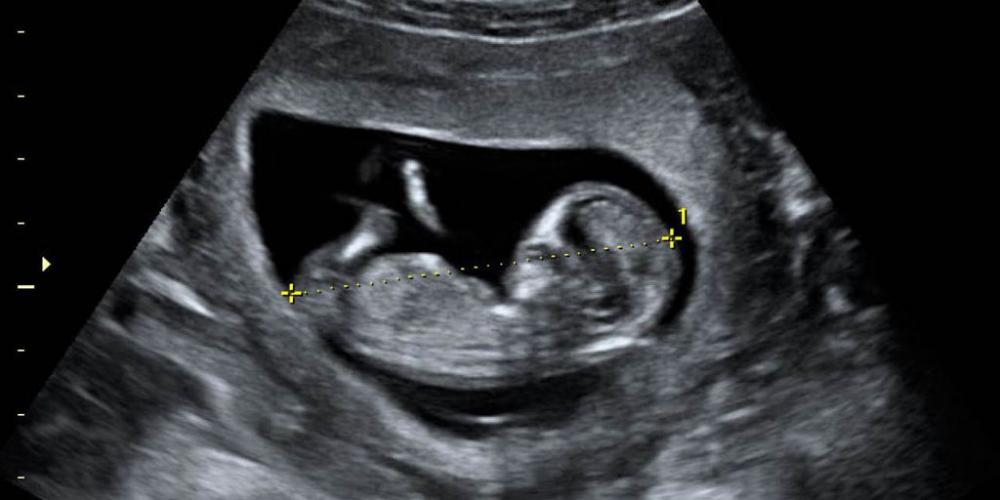

EN BUENOS AIRES MUEREN MÁS DE 90 NIÑOS ANTES DE NACER POR DÍA

En 2021 el 92% de los abortos en la provincia de Buenos Aires se hicieron con la droga Misoprostol. Desde que Axel Kicillof (50) gobierna la provincia de Buenos Aires fueron incorporados 298 nuevos sitios (hospitales...